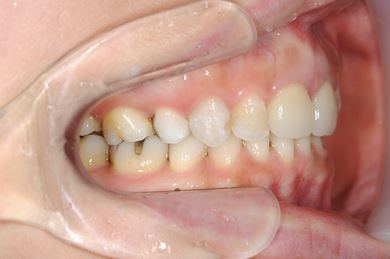

セラミックの症例写真 SHINBI

インプラント矯正治療+セラミック治療

| 性別/年齢 | 女性 / 35歳 | ||||||||||||||||||||||||||||||||

| 主訴 | 歯並び(乱ぐい歯、出っ歯)と歯の色が気になる。 | ||||||||||||||||||||||||||||||||

| 治療方針 | 左上の第一大臼歯がすでに抜歯され欠損の状態で来院されました。デンタルインプラント、あるいはブリッジで補綴するよりも、上あごが突出していること、乱杭歯があることより、矯正治療を第一選択としました。上下第一小臼歯を4本抜歯してその隙間を利用し、治療していきました。抜歯スペースをすべて効率的に利用したいため、上顎左右、下顎左側1本の計3本のインプラントアンカーを使用します。左上は第二大臼歯、智歯を利用しています。今後保定装置の針金は一生装着予定です。上顎の中切歯は左右とも人工的にかぶせものをしています。初診の歯牙変色がなくなり、審美的にもとてもよくなりました。 | ||||||||||||||||||||||||||||||||

| 治療内容 | インプラント矯正(唇側矯正ホワイト、審美ワイヤー、左右上顎第一小臼歯抜歯、上顎インプラントアンカー) | ||||||||||||||||||||||||||||||||

| 治療期間 | 1年9ヶ月 |